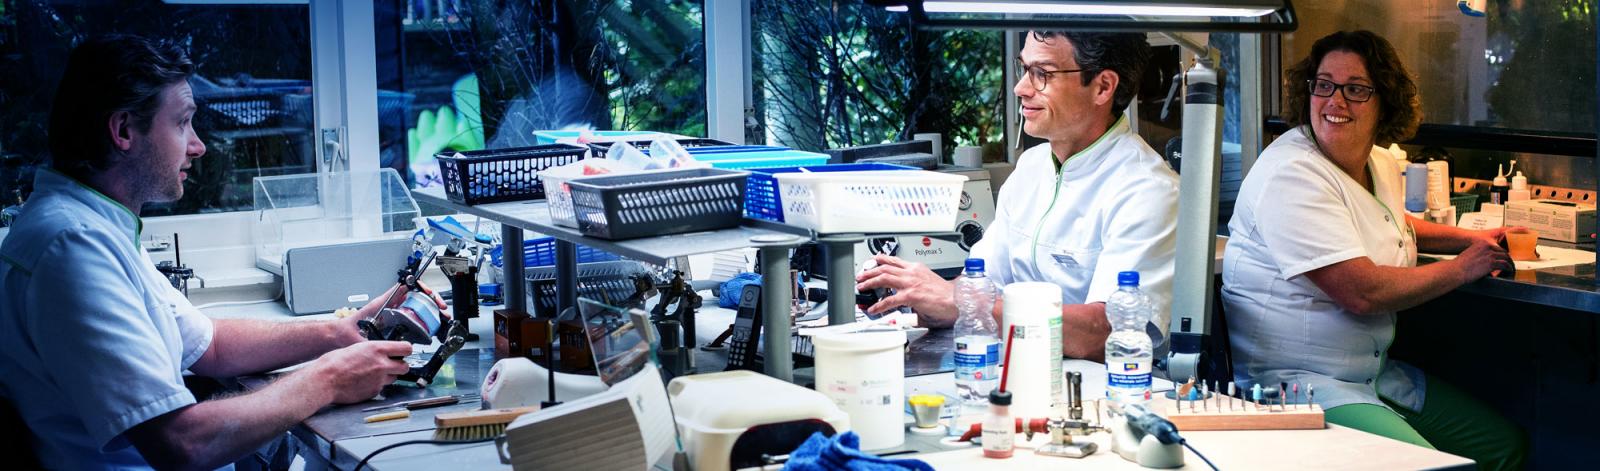

Een klikgebit is een kunstgebit dat vast zit op implantaten. Implantaten zijn kunstwortels die in de kaak geplaatst worden als een schroef. Er zijn verschillende systemen waarop het kunstgebit op de implantaten vast gezet kunnen worden, hieronder ziet u de twee meest voorkomende systemen.

De implantaten zullen dan eerst geplaatst worden en daarna maken wij voor u het klikgebit op de implantaten.